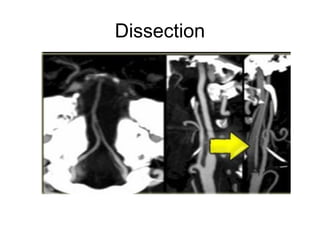

Dissection